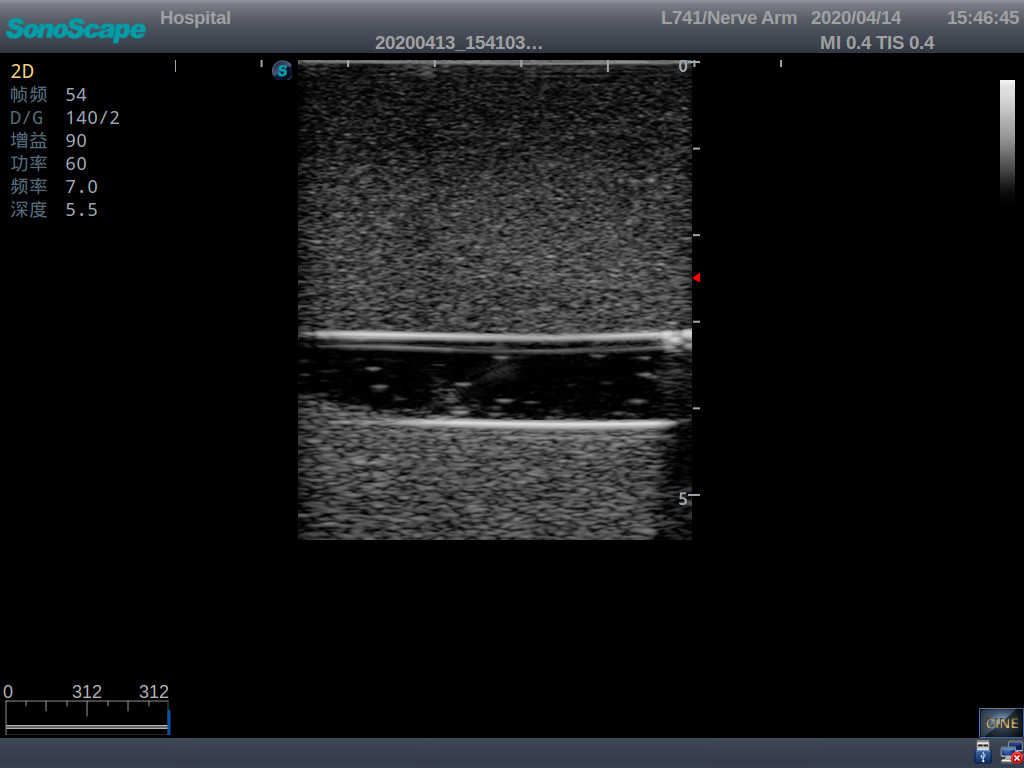

3)   Clear and real images of the tissues and organs (basilic vein and superior vena cava)

5)   Observe the guide wire marches

6)   Detect whether the catheter is properly placed